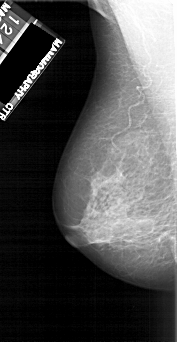

A_1118_1.RIGHT_MLO

LEFT_MLO LINES 5116 PIXELS_PER_LINE 2641 BITS_PER_PIXEL 12 RESOLUTION 43.5 NON_OVERLAY